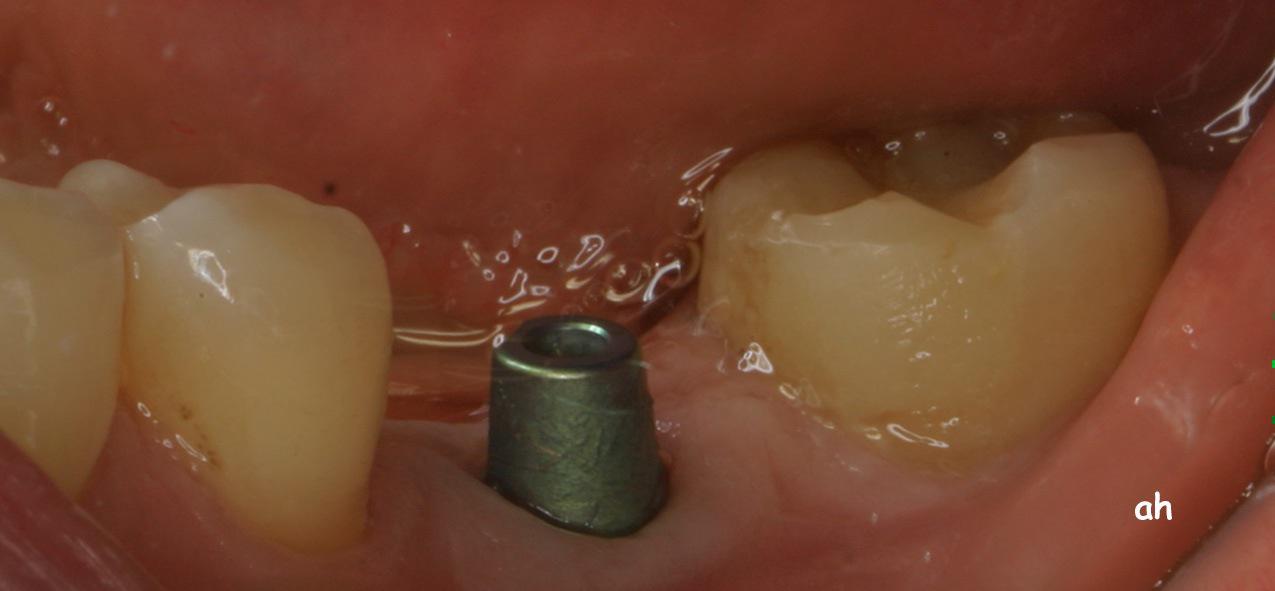

Exemple 11: Après cicatrisation environ 6 mois, le moignon est vissé sur l'implant.

Exemple 11: La couronne céramique en place.